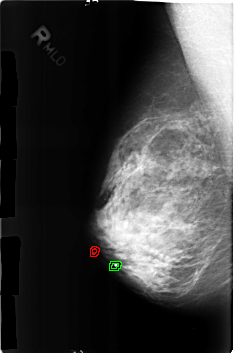

B_3168_1.RIGHT_MLO

RIGHT_MLO LINES 4584 PIXELS_PER_LINE 3056 BITS_PER_PIXEL 12 RESOLUTION 50 OVERLAY

FILE: B_3168_1.RIGHT_MLO.OVERLAY

TOTAL_ABNORMALITIES 2

ABNORMALITY 1

LESION_TYPE CALCIFICATION TYPE COARSE DISTRIBUTION N/A

ASSESSMENT 2

SUBTLETY 4

PATHOLOGY BENIGN_WITHOUT_CALLBACK

TOTAL_OUTLINES 1

BOUNDARY

ABNORMALITY 2